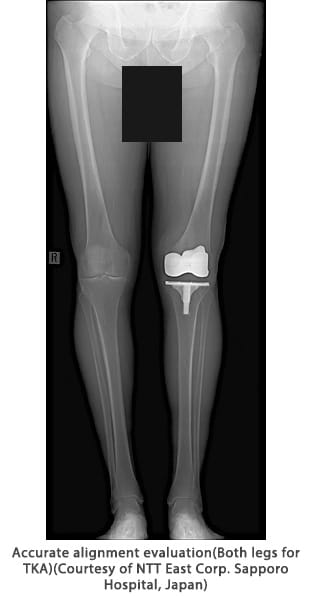

This application enables simple operation, large imaging area, and easy-to-interpret images. It is available with Shimadzu R/F system and general radiography systems and provides efficient examination and accurate diagnosis.